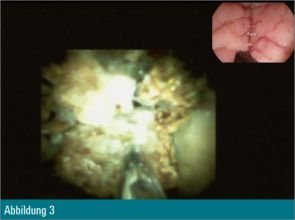

Trotz Fragmentierung des Konkrements (Abbildung 4) waren mehrfache mechanische Lithotripsien mit dem Dormiakörbchen in derselben Sitzung notwendig. Schlussendlich konnten alle Fragmente erfolgreich mit dem Ballon geborgen werden (Abbildung 5).